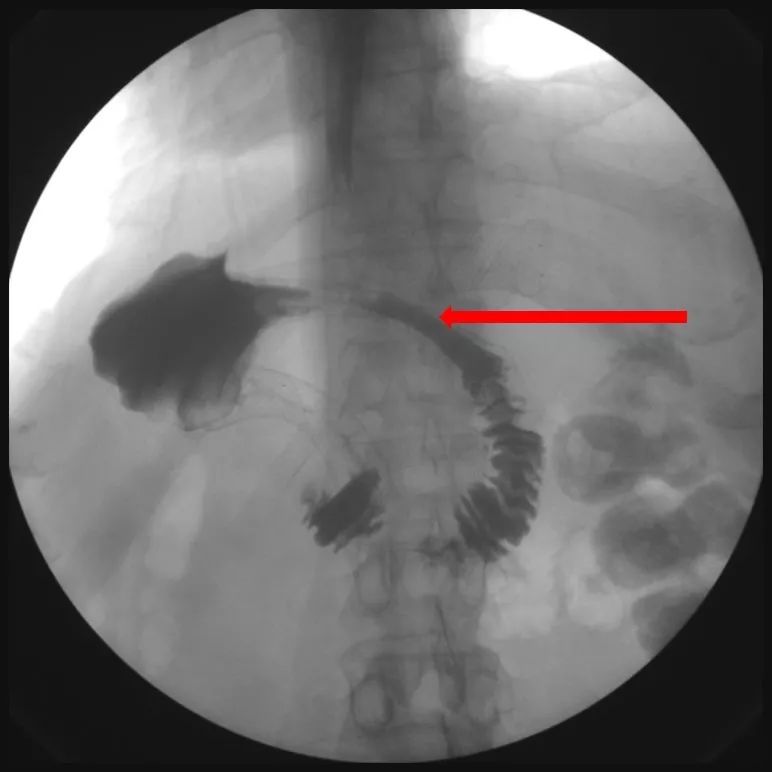

征得患者及家属同意后,于2019-1-10为患者放置结肠支架。术中结肠镜见结肠脾曲充血水肿,内镜无法通过。未见明确的肿物。结肠支架放置过程顺利,术后复查X线平片,见扩张的结肠回缩,造影剂通过了结肠脾曲(图23)。

图23 两支架就位良好,肠梗阻缓解,扩张的横结肠回缩,造影剂通过结肠脾曲